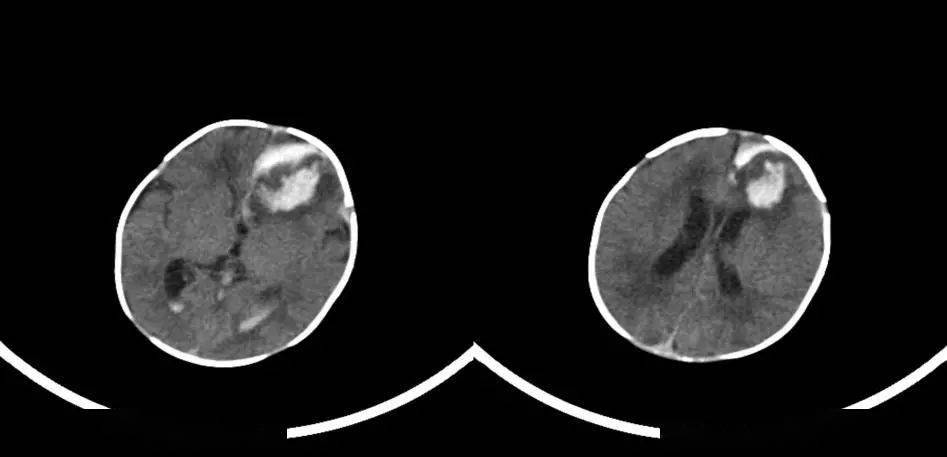

超研股份董秘:您好,公司致力于将超声和射线技术应用在各领域以满足用户的不同需求,超声在颅脑方面的应用是公司研发的重点之一,在这方面也已经取得了多项专利和软件著作权,详细可查阅公司招股书和定期报告。目前公司有多种型号的超声诊断产品可应用于颅脑方面的检查。感谢您的关注!